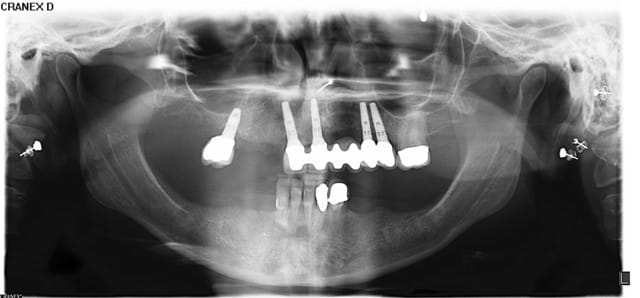

Patiente adressée pour évaluation :

son dentiste ne sait que faire.

À l'examen :

13 : belle fistule vestibulaire, mobilité, carie cervicale

14 : mobilité +++

15 : fracture racine (?), carie cervicale

Les implants datent de 5-6 ans (par un autre CD, la patiente a depuis déménagée).

Le bas , pas touche cette année, on verra en 2012.

Votre plan de tx ?

flicflac

08/04/2011 à 05h57

je le réfère à Céramik, il pose des implants...

Panorex avec Vitallium en bouche ok... au moins on sait que la patiente possède un partiel...

mobilité dent 14 sondage=?... perte sûre de la 15, endo et reprise couronne dent 13

pluton

09/04/2011 à 09h42

et pour la suite, c'est 2 implants et bridge 13/15? (difficile d'avoir des certitudes quand au nombre d'implants...sans avoir tous les éléments...)

le bond bone, çà marche bien?